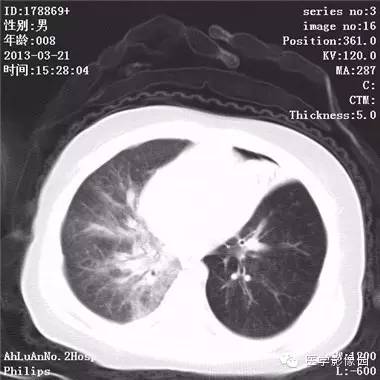

患儿男,8个月,呛咳,发热一周。实验室检查白细胞及中性粒细胞增高。

两肺肺纹理增多、增粗,右肺可见斑片状、片絮状模糊影,边界欠清;左肺上叶见楔形高密度影,内可见支气管征,尖端指向肺门;左肺下叶肺野透亮度增强;另见左肺主支气管内可见块状软组织密度影。

支气管异物(花生米)伴两肺炎症(追问病史,患儿奶奶层于一周前喂食患儿花生米,当时疑似“呛进去”,后来见好了也就没留意)。